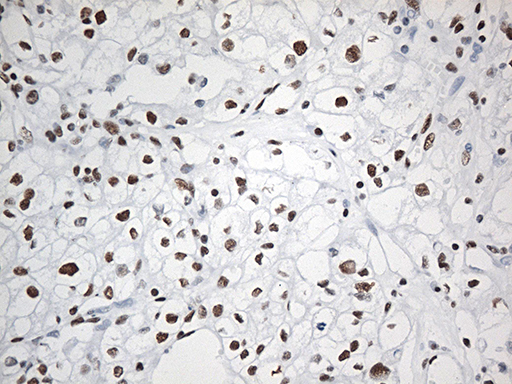

Facts about RNA-binding protein EWS.

| Gene Name: | EWSR1 |